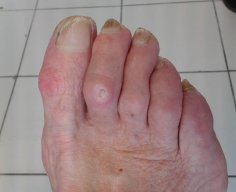

Appareillages d'Orteils : Orthoplasties

Les orthoplasties

Sont des appareillages d'orteils amovibles, sur mesure, destinés à traiter les déformations d'orteils et leurs conséquences.

Les orthoplasties correctrices corrigent une déformation réductible ou une malposition (sur ces photos)

Les orthoplasties protectrices protègent une zone douloureuse afin d’éviter les conflits peau/chaussure.